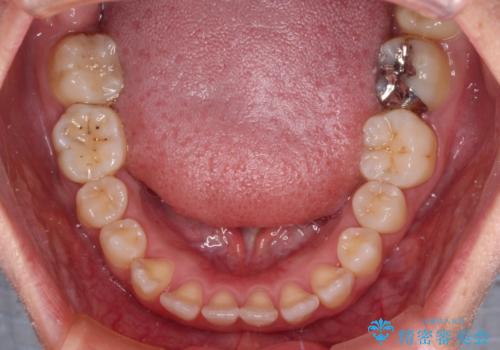

- 全顎的なクロスバイトと反対咬合を気にして来院された患者様です。

骨格的に下顎が前方位にありましたが、歯並びにより下顎が本来の位置よりも前方位に誘導される咬み合わせとなっていました。

上顎歯列および上顎骨が下顎に対して狭小であることが原因であるため、上顎の急速拡大装置を使用して上顎骨を側方に拡大することで反対咬合を改善し、ワイヤー装置で歯列を整えることとしました。